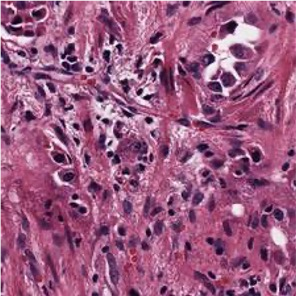

Multiple instance learning (MIL) is a powerful approach to classify whole slide images (WSIs) for diagnostic pathology. A fundamental challenge of MIL on WSI classification is to discover the \textit{critical instances} that trigger the bag label. However, previous methods are primarily designed under the independent and identical distribution hypothesis (\textit{i.i.d}), ignoring either the correlations between instances or heterogeneity of tumours. In this paper, we propose a novel multiplex-detection-based multiple instance learning (MDMIL) to tackle the issues above. Specifically, MDMIL is constructed by the internal query generation module (IQGM) and the multiplex detection module (MDM) and assisted by the memory-based contrastive loss during training. Firstly, IQGM gives the probability of instances and generates the internal query (IQ) for the subsequent MDM by aggregating highly reliable features after the distribution analysis. Secondly, the multiplex-detection cross-attention (MDCA) and multi-head self-attention (MHSA) in MDM cooperate to generate the final representations for the WSI. In this process, the IQ and trainable variational query (VQ) successfully build up the connections between instances and significantly improve the model's robustness toward heterogeneous tumours. At last, to further enforce constraints in the feature space and stabilize the training process, we adopt a memory-based contrastive loss, which is practicable for WSI classification even with a single sample as input in each iteration. We conduct experiments on three computational pathology datasets, e.g., CAMELYON16, TCGA-NSCLC, and TCGA-RCC datasets. The superior accuracy and AUC demonstrate the superiority of our proposed MDMIL over other state-of-the-art methods.